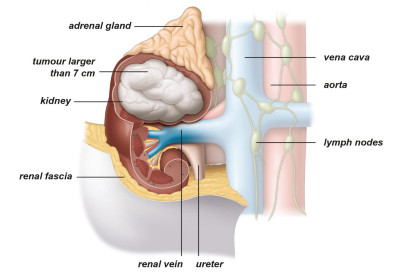

Εντοπισμένο ονομάζουμε τον καρκίνο που εξακολουθεί να περιορίζεται εντός των ανατομικών ορίων του νεφρού, χωρίς να έχει επεκταθεί σε άλλες ανατομικές δομές, όπως λεμφαδένες ή άλλα όργανα (Εικ. 3,4).

Εικ. 4: Όγκος σταδίου ΙΙ

Ο εντοπισμένος καρκίνος του νεφρού μπορεί να αφαιρεθεί είτε μέσω μερικής νεφρεκτομής είτε μέσω ριζικής νεφρεκτομής. Και οι δύο επεμβάσεις μπορούν να πραγματοποιηθούν με ανοικτή, λαπαροσκοπική ή ρομποτική χειρουργική.

Κατά τη διάρκεια μιας μερικής νεφρεκτομής αφαιρείται μόνο ο όγκος (ογκεκτομή), αφήνοντας τον υγιή ιστό των νεφρών ανέπαφο. Αυτή η χειρουργική επέμβαση συνιστάται όποτε είναι πρακτικά εφικτό. Εάν δεν είναι δυνατόν να αφαιρεθεί μόνο ο όγκος και να παραμείνει άθικτο μέρος του νεφρού, τότε η θεραπεία εκλογής είναι η ριζική νεφρεκτομή. Αυτό σημαίνει ότι ο νεφρός στον οποίο βρίσκεται ο όγκος και ο περιβάλλων ιστός αφαιρούνται εντελώς.